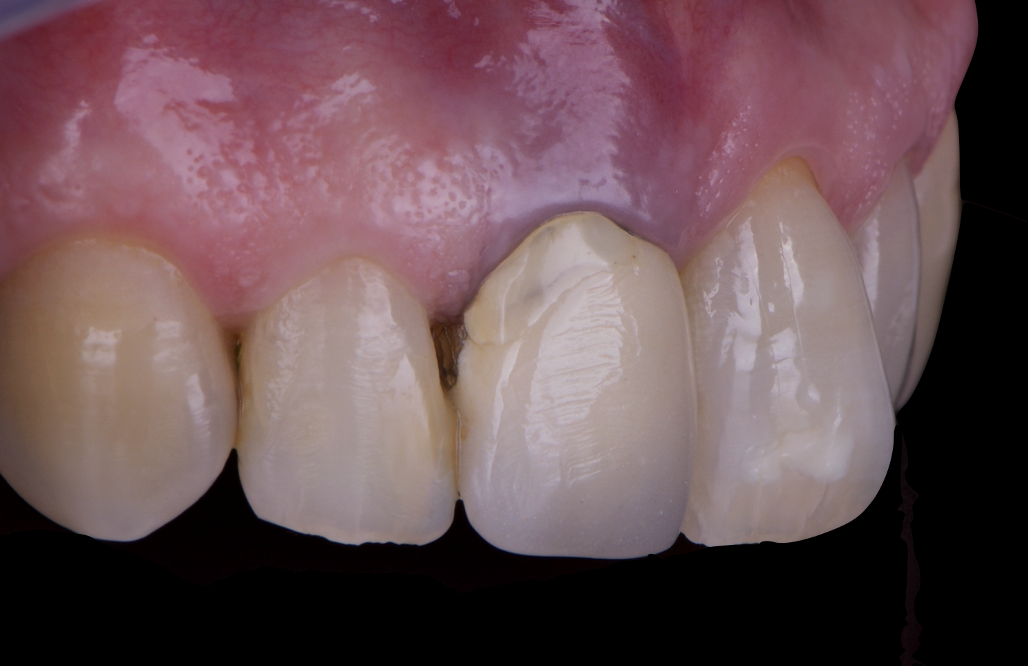

On the same day as the surgery, an immediate-load provisional crown was delivered. This restoration was fabricated in acrylic resin and screw-retained on the implant, following the “one abutment one time” principle. The provisional crown was carefully adjusted to avoid occlusal loading while supporting the peri-implant soft tissue architecture during the healing phase.

The provisional not only satisfied the patient’s functional and esthetic demands but also played a key role in shaping the emergence profile and conditioning the gingival margin. By providing a provisional solution immediately, the patient was able to leave the clinic with a natural-looking smile, avoiding any psychological or social impact associated with tooth loss in the anterior maxilla.